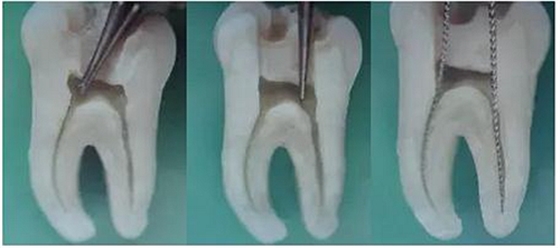

1.開髓:洞型是否制備的符合要求,髓室頂是否揭得剛剛好,沒有破壞洞壁及洞底結(jié)構(gòu)。

圖1裂鉆鉆到近髓 圖2球鉆穿髓 圖3小號銼探查根管口

圖4 球鉆揭髓頂 圖5修整洞型 圖6完成開髓